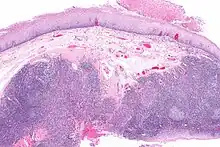

Histopathologic appearance of a poorly differentiated squamous cell carcinoma specimen. Hematoxylin-eosin stain. p16 positive, EBV negative

Diagnosis of oral cancer is completed for (1) initial diagnosis, (2) staging, and (3) treatment planning. A complete history, and clinical examination is first completed, then a wedge of tissue is cut from the suspicious lesion for tissue diagnosis. This might be done with scalpel biopsy, punch biopsy, fine or core needle biopsy. In this procedure, the surgeon cuts all, or a piece of the tissue, to have it examined under a microscope by a pathologist.[33] Brush biopsies are not considered accurate for the diagnosis of oral cancer.[34]

With the first biopsy, the pathologist will provide a tissue diagnosis (e.g. squamous cell carcinoma), and classify the cell structure. They may add additional information that can be used in staging, and treatment planning, such as the mitotic rate, the depth of invasion, and the HPV status of the tissue.